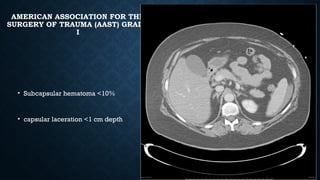

AMERICAN ASSOCIATION FOR THE

SURGERY OF TRAUMA (AAST) GRADE

I

• Subcapsular hematoma <10%

• capsular laceration <1 cm depth

AMERICAN ASSOCIATION FORTHE SURGERY OF TRAUMA (AAST) GRADE I • Subcapsular hematoma <10% • capsular laceration <1 cm depth